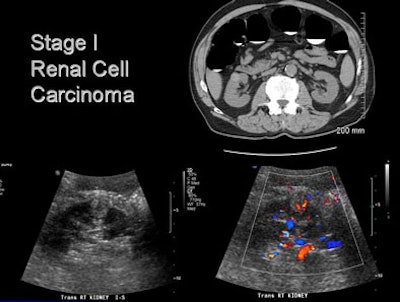

- Renal cell carcinoma (n = 4)

![]() |

| A man in his 70s underwent CT colonography screening; MDCT revealed a large renal mass. Workup also revealed multiple lung nodules. He was diagnosed with metastatic renal cell carcinoma; however, no intervention has been performed due to multiple comorbidities, and the patient has done well. |